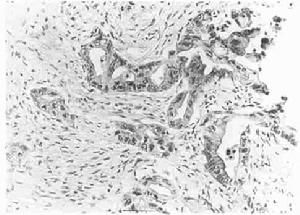

1.組織活檢病理學檢查

組織活檢病理學檢查可引起大出血應慎重使用。